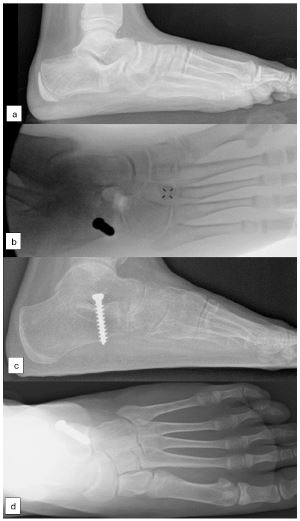

The author’s preferred method of arthroereisis involves the insertion of a 6.5 mm cancellous bone screw (AO large fragment set) near the anterolateral edge of the posterior facet of the subtalar joint, positioned under the lateral process of the talus. This screw functions as a calcaneo-stop screw, preventing excessive hindfoot eversion and maintaining the subtalar joint in a more aligned position (Figure 1). At the end of procedure, the foot alignment evaluated to exclude hindfoot valgus overcorrection. The decision of gastrocnemius recession was made at the end of the procedure based on Silfverskiöld test.

Figure 1: Preoperative standing radiograph of calcaneo-navicular coalition (A); Intraoperative fluorogram (B); Corrected calcaneal pitch, talo-navicular coverage and Meary’s angle after coalition excision and arthroereisis (C,D).